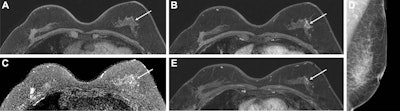

Researchers led by Soo-Yeon Kim, PhD, from Seoul National University Hospital, compared the performance of abbreviated MRI and full-protocol MRI in two separate cohorts of 726 patients. They found a statistically significant improvement in specificity for the group of patients receiving abbreviated MRI. Although abbreviated MRI also yielded better sensitivity, cancer detection rate, interval cancer detection rate, and positive predictive value, those results did not reach statistical significance.

In other findings, researchers also found that 93% (14 of 15) of cancers detected at abbreviated MRI were node-negative T1-invasive cancers (n = 6) or ductal carcinoma in situ (DCIS) (n = 8).